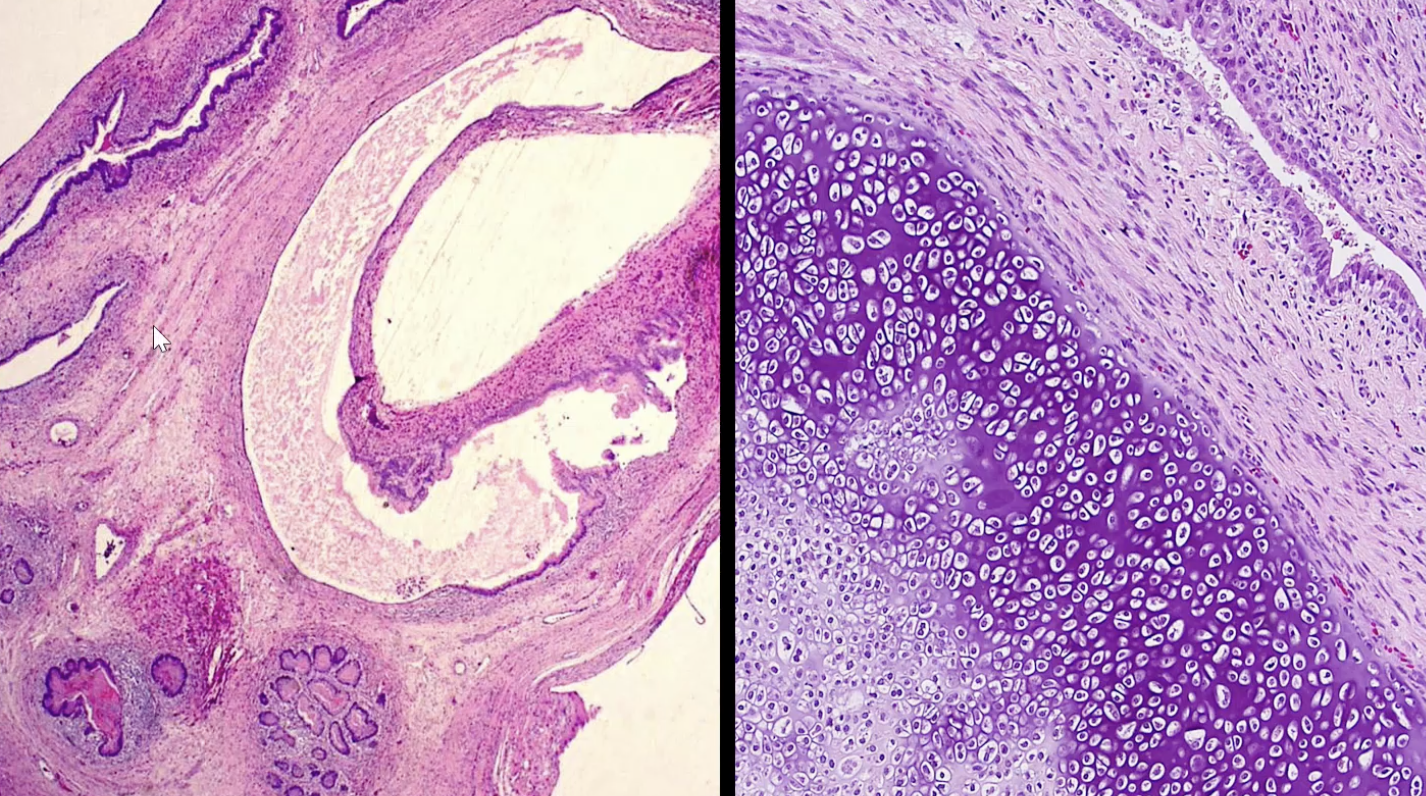

Teratoma

Mature teratoma - better prognosis

Immature teratoma - worse prognosis